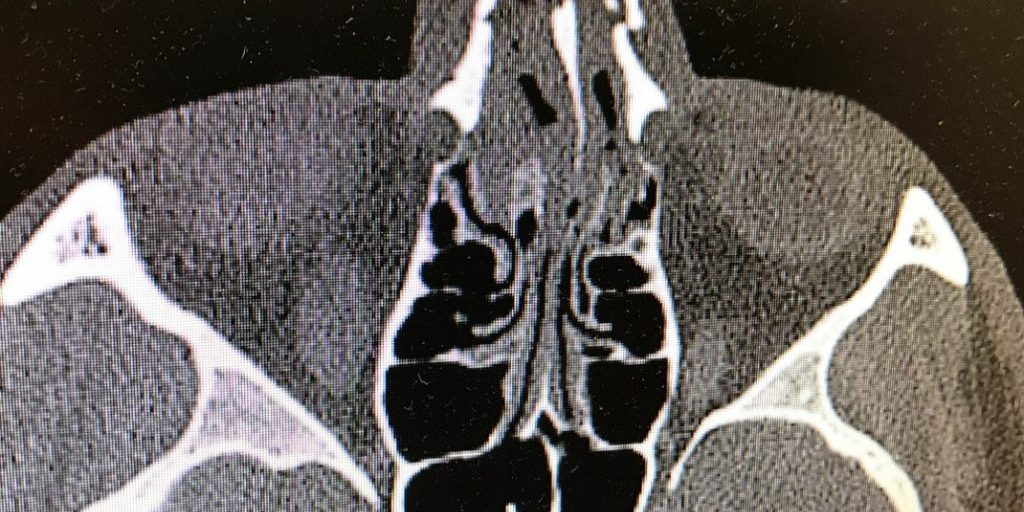

На приёме врач оценивает признаки, указывающие на перелом: подвижность костей носа, степень отека, гематомы, деформацию тканей. Для исключения осложнений могут быть назначены дополнительные диагностические процедуры: рентген или компьютерная томография костей носа, общий анализ крови (оценка степени кровопотери и наличия воспалительного процесса), биохимический анализ крови, коагулограмма (оценка свертывающей функции крови), общий анализ мочи.